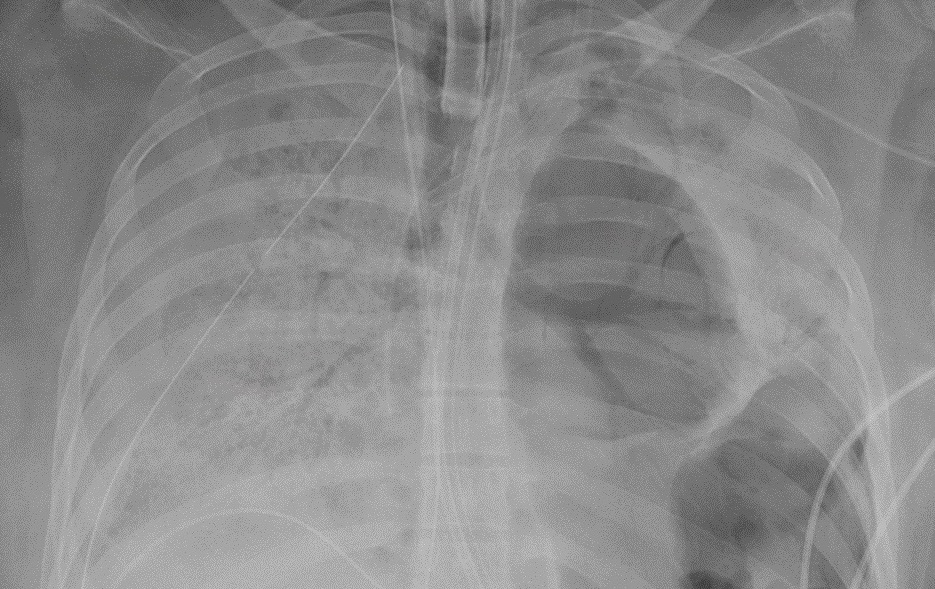

The Role Of Chest Radiography In Confirming Covid 19 Pneumonia The Bmj

www.bmj.com

Coronavirus What X Rays And Ct Scans Reveal About How Covid 19 Kills Science Tech News Sky News

news.sky.com

X Ray Imaging For Covid 19 Patients Siemens Healthineers Saudi Arabia

www.siemens-healthineers.com

X Ray Identifies More Air Pressure Lung Injuries In Covid 19 Patients

www.diagnosticimaging.com